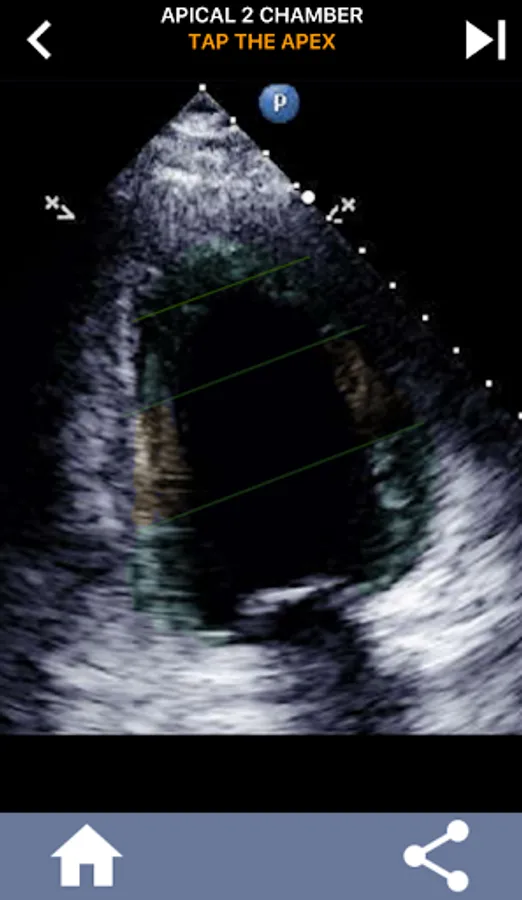

This app will test your knowlegde using actual echo images, which I often find to be the best teaching method.